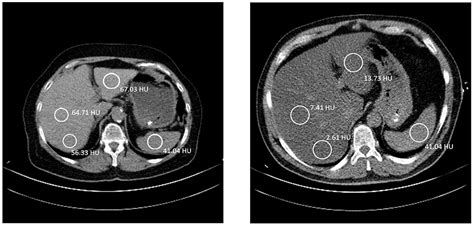

Unlocking Fatty Liver: Your CT Scan Guide Hey guys, ever heard the phrase ‘fatty liver’ and wondered what it truly means, especially when your doctor mentions a CT scan ? You’re definitely not alone! It’s a super common condition, often silent and sneaky, but understanding it is a huge step towards better health. Think of your liver as one of your body’s unsung heroes – it’s always busy detoxifying, producing proteins, and helping with digestion. When it starts accumulating too much fat, that’s when we call it fatty infiltration of the liver , or medically, hepatic steatosis . It’s a condition that can range from a mild, almost harmless state to something more serious if left unchecked, potentially progressing to inflammation, scarring, and even cirrhosis . That’s why getting a clear diagnosis and understanding what’s going on inside is so important. And this is where a CT scan really shines as a key diagnostic tool. This article is all about demystifying the CT scan process, explaining what your doctor is looking for, and helping you understand what your results might mean. We’ll dive into the nitty-gritty of how these scans work to detect fatty liver , what those fancy medical terms like ‘Hounsfield Units’ actually refer to, and why a comparison to your spleen might be relevant. Our goal here is to empower you with knowledge, making sure you feel informed and ready to discuss your liver health with your healthcare provider. So, let’s pull back the curtain on fatty liver and CT scans together, ensuring you have the lowdown on taking control of your well-being. Getting to grips with how medical imaging can reveal important insights about your internal organs, especially something as vital as your liver, is incredibly beneficial for anyone navigating their health journey. We’re going to break down complex medical jargon into easy-to-digest info, making sure you feel confident and prepared for those conversations with your doctor. Understanding the diagnostic tools available, like the CT scan , can truly make a difference in how you approach your overall liver health and the steps you take towards a healthier future. So buckle up, because we’re about to make understanding your liver and its health a whole lot clearer! We’ll cover everything from what causes fatty liver to what you can do about it, all through the lens of how a CT scan helps paint that crucial picture. This journey of understanding begins now, and it’s all about equipping you with the best information to advocate for your own health. Ready? Let’s go! # What Exactly is Fatty Liver, Anyway?Alright, let’s start with the basics. What exactly is fatty liver , also known as hepatic steatosis ? Simply put, it’s a condition where too much fat builds up in your liver cells. Now, having a tiny bit of fat in your liver is totally normal, guys. Your liver is a busy organ, involved in practically everything from processing nutrients to filtering toxins. However, when fat accounts for more than 5-10% of your liver’s weight, that’s when we officially call it fatty infiltration of the liver . This isn’t just some abstract medical term; it represents a real change in how your liver functions and looks. The scary part? Often, fatty liver doesn’t cause any noticeable symptoms in its early stages. You might not feel a thing, which is why it’s sometimes called a silent disease. But don’t let its quiet nature fool you; it’s a condition that warrants attention. There are two main types of fatty liver : alcoholic fatty liver disease (AFLD), caused by heavy alcohol consumption, and non-alcoholic fatty liver disease (NAFLD), which, as the name suggests, isn’t linked to alcohol. NAFLD is incredibly common, affecting about one-quarter of the global population, and its prevalence is rising rapidly alongside rates of obesity, type 2 diabetes, and metabolic syndrome. If you’ve ever heard of conditions like high blood pressure, high cholesterol, or insulin resistance, these are often buddy-buddy with NAFLD. The progression of NAFLD can be concerning. While simple fatty liver (steatosis) is generally considered benign, it can progress to non-alcoholic steatohepatitis (NASH), where inflammation and liver cell damage occur alongside the fat. This inflammation can lead to fibrosis (scarring), which, if severe enough, can turn into cirrhosis – a serious, irreversible form of liver damage that can impair liver function and even lead to liver failure or liver cancer. Understanding this potential progression is crucial for appreciating why early detection and management of fatty infiltration of the liver are so vital. It’s not just about seeing fat; it’s about preventing a cascade of more severe liver disease . This understanding sets the stage for why tools like the CT scan are so important in diagnosing and monitoring this condition. We’re talking about taking proactive steps to safeguard one of your most critical organs, and it all starts with recognizing what fatty liver is and why it matters to your overall health. It’s truly a journey towards better liver health , and knowing the enemy is the first step in winning the battle. So, when your doctor mentions fatty liver , remember it’s a signal to pay attention to your lifestyle and well-being. # The Role of CT Scans in Diagnosing Fatty Liver Okay, so we know what fatty liver is. Now, let’s talk about how we actually see it. This is where the mighty CT scan comes into play. You might be wondering,